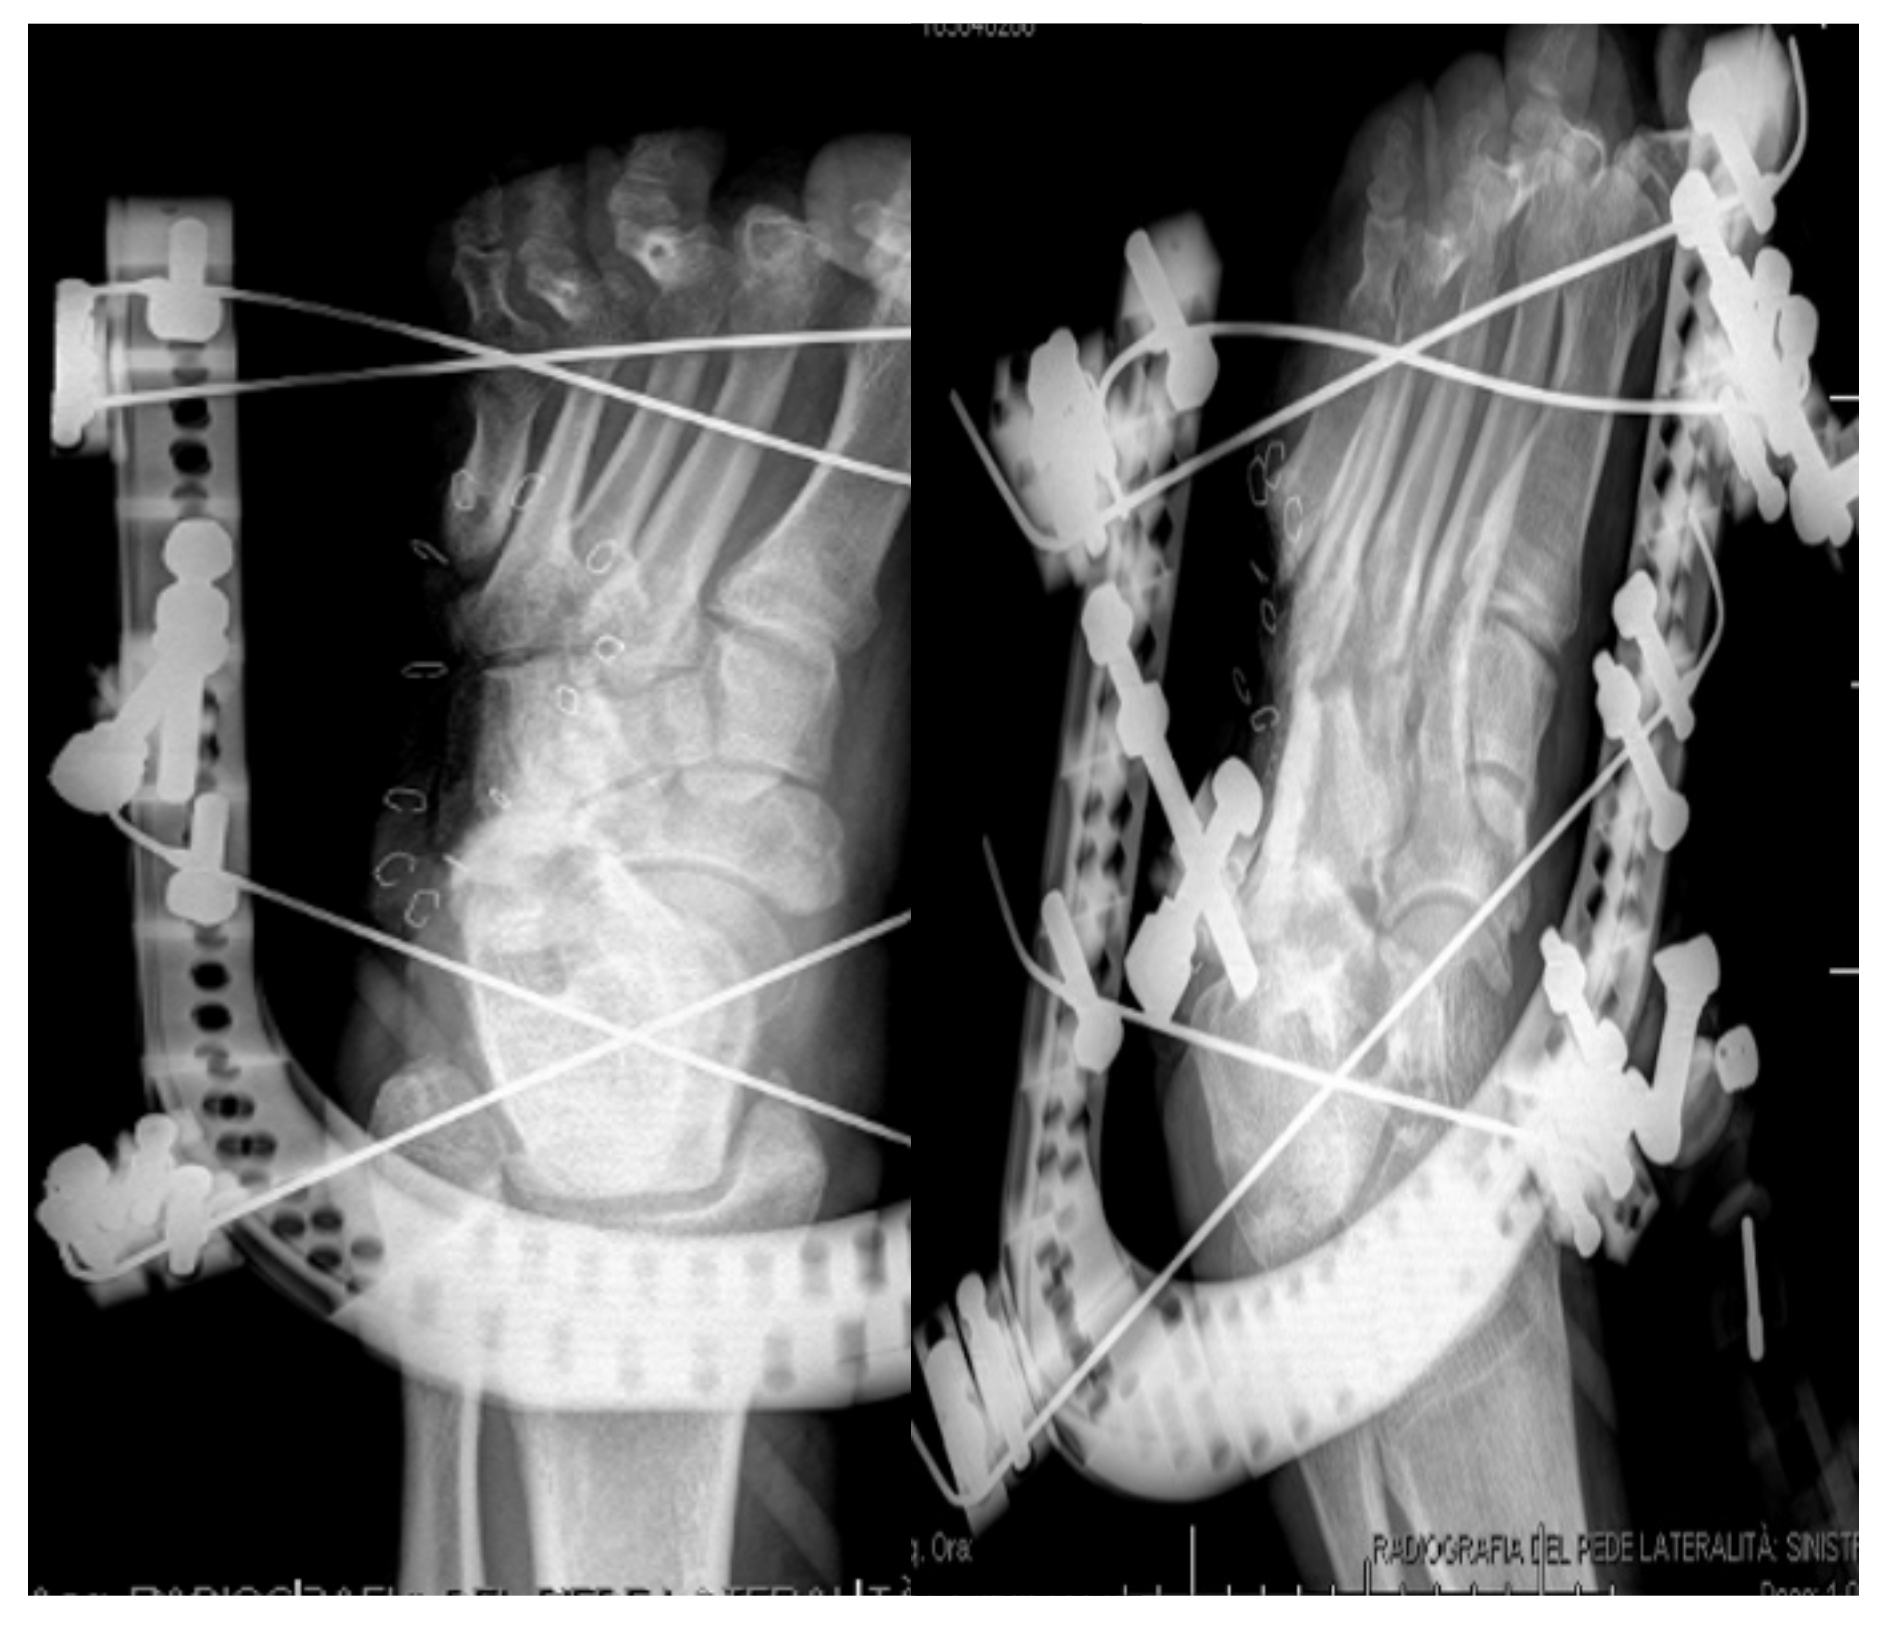

3.3. Lesions Involving Distal Tarsus & Talus